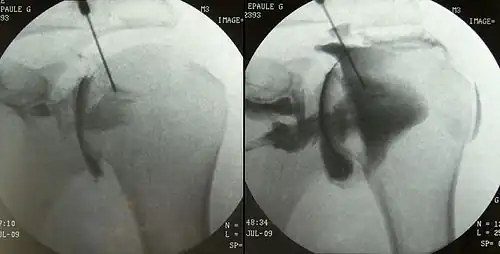

Arthrographie d'une épaule gauche.

L'arthrographie est une radiographie avec préparation. La préparation consiste à faire pénétrer une substance opaque aux rayons X dans l'articulation que l'on désire explorer radiologiquement notamment pour détecter des anomalies dans la capsule articulaire. Après l'injection du produit de contraste (iodés) dans l'articulation, on prend des cliches de celle-ci de face, de profil ou oblique avec plusieurs degrés d'inclinaison.